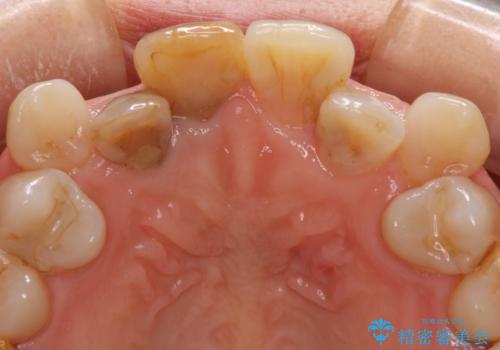

変色した前歯のオールセラミック治療

- 前歯の変色が気になるとのことで来院された患者様です。

歯並びに問題があるため、矯正治療の提案をしましたが、変色の改善のみ(オールセラミッククラウンによる審美補綴治療のみ)とすることにしました。

矯正治療を行う必要性は理解いただきましたが、「今さら歯並びを整えても・・・」という思いが強かったようで、何度もカウンセリングを行った結果、審美補綴治療のみとなりました。

お粗末な根管治療、根管充填がされていたため、補綴治療を行うにあたり根管治療を行いました。